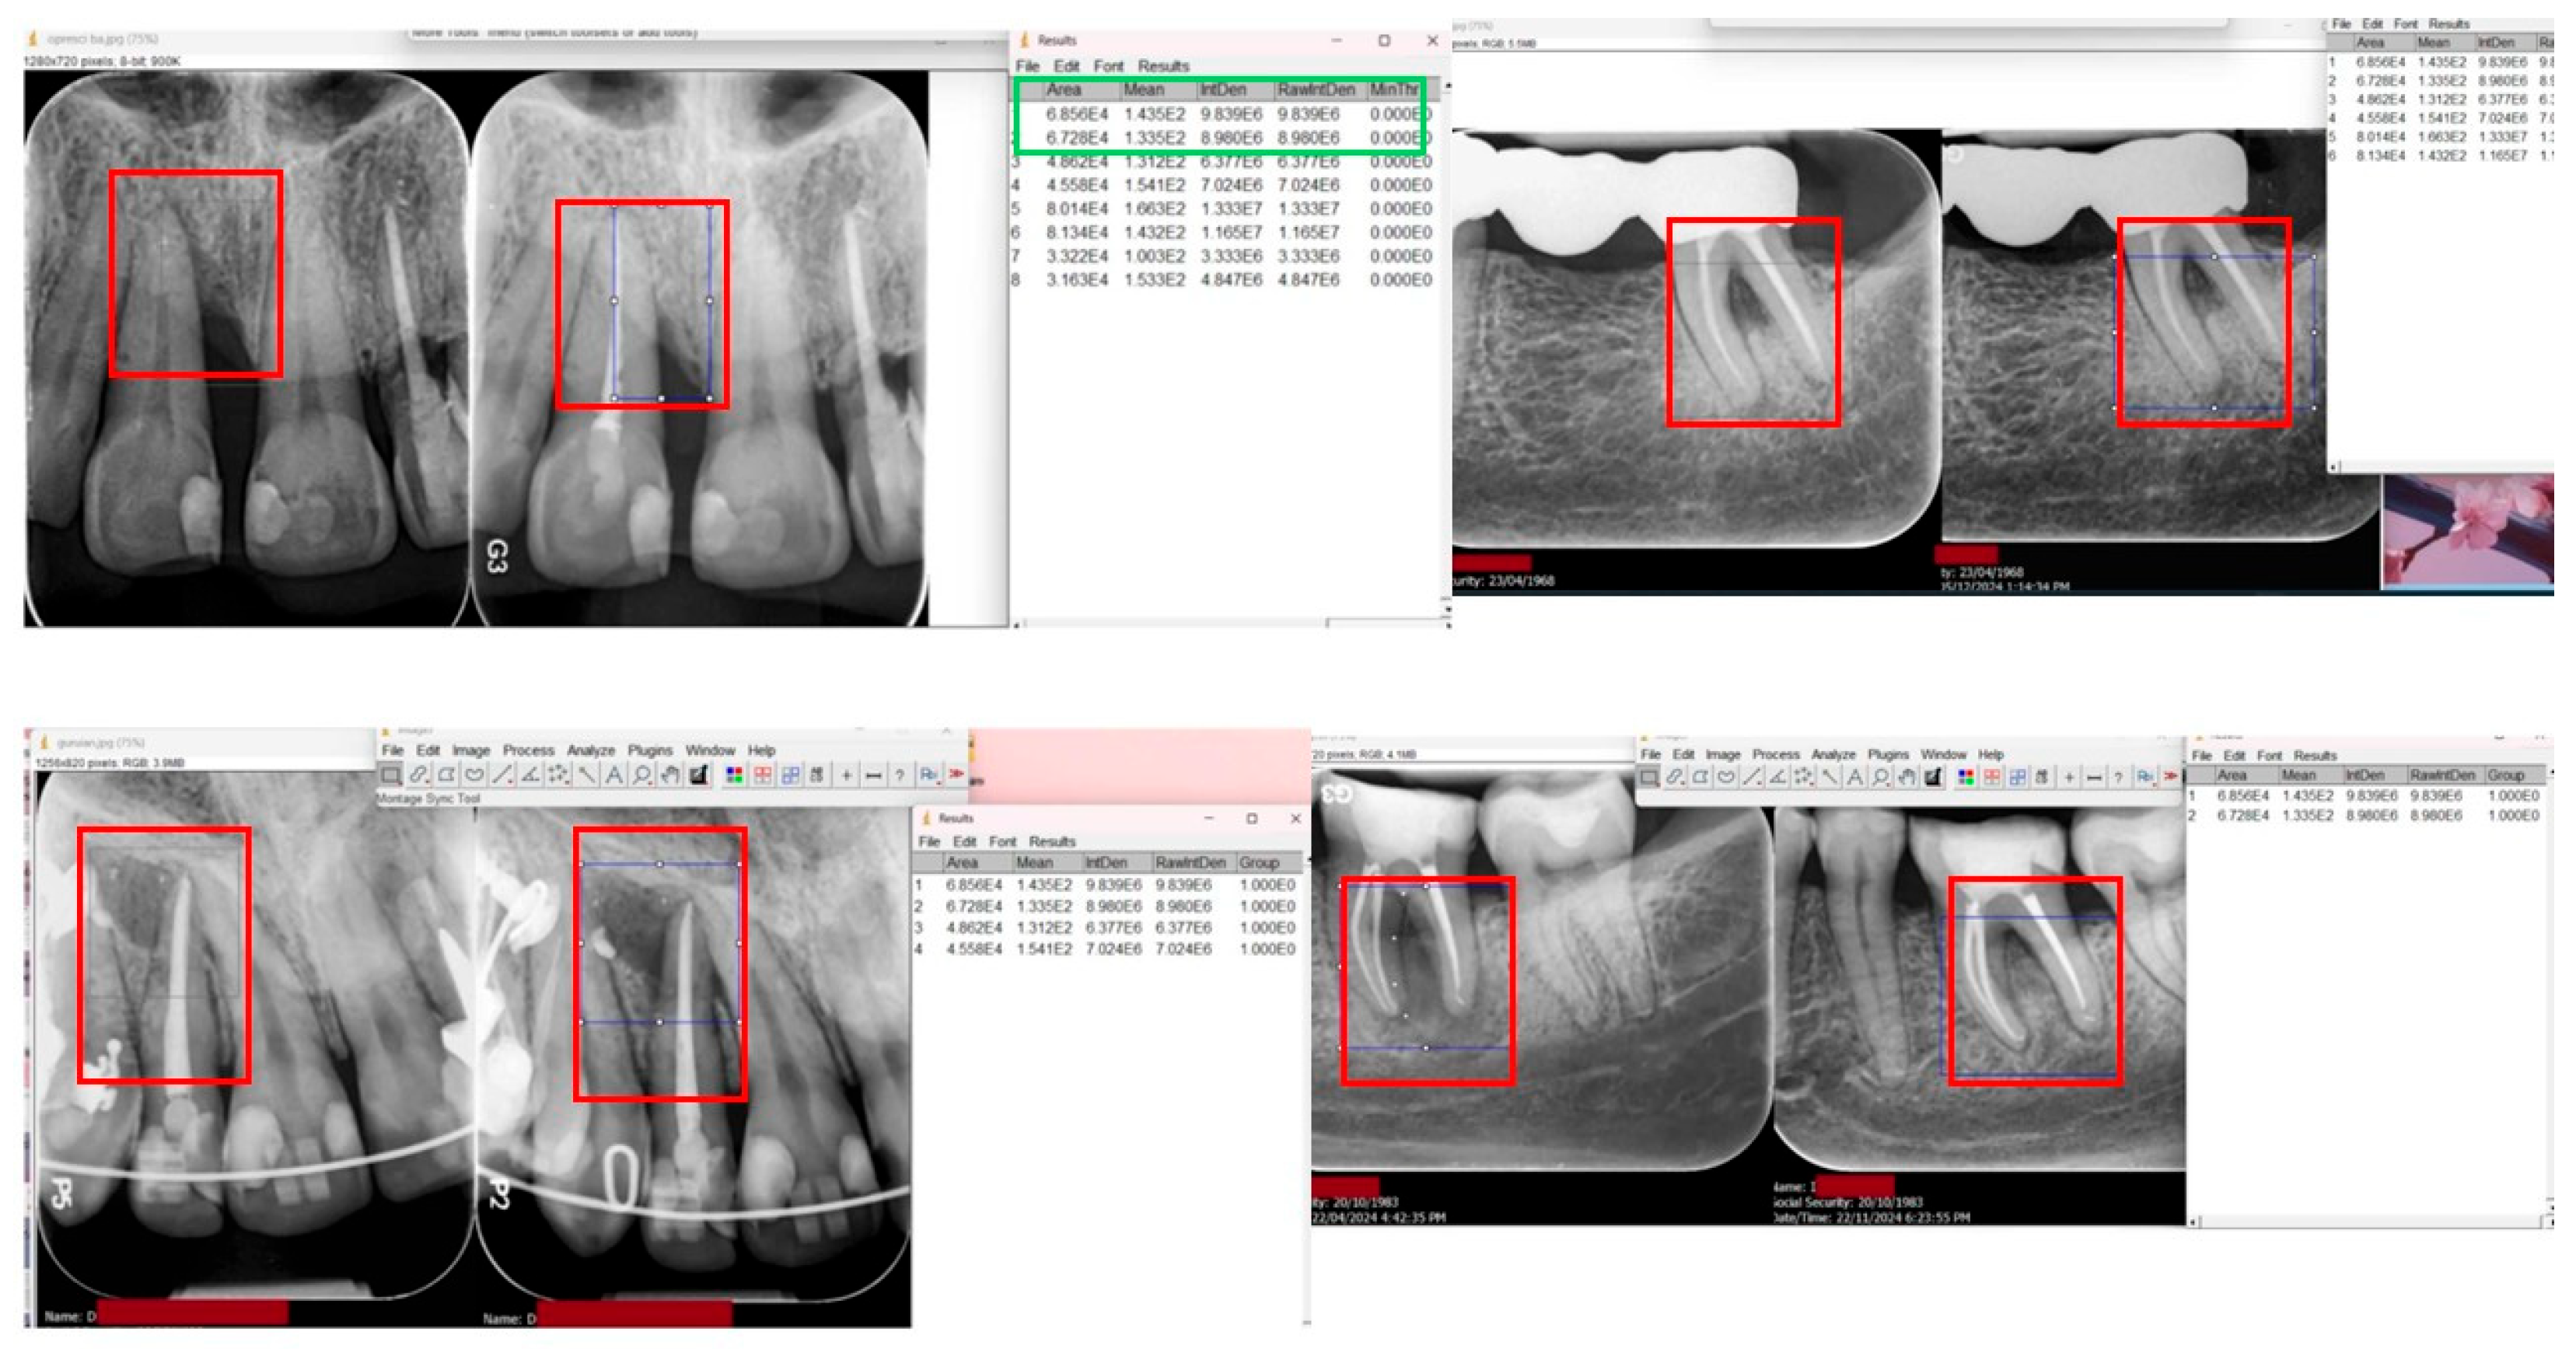

Radiographic Evaluation

| ROI | Region of interest (for image analysis) |